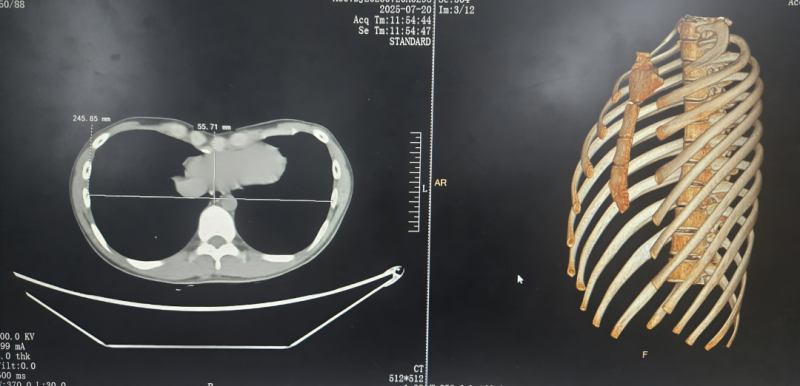

漯河市中心医院成功为13岁少年实施肺隔离症合并漏斗胸联合矫治术

09/17